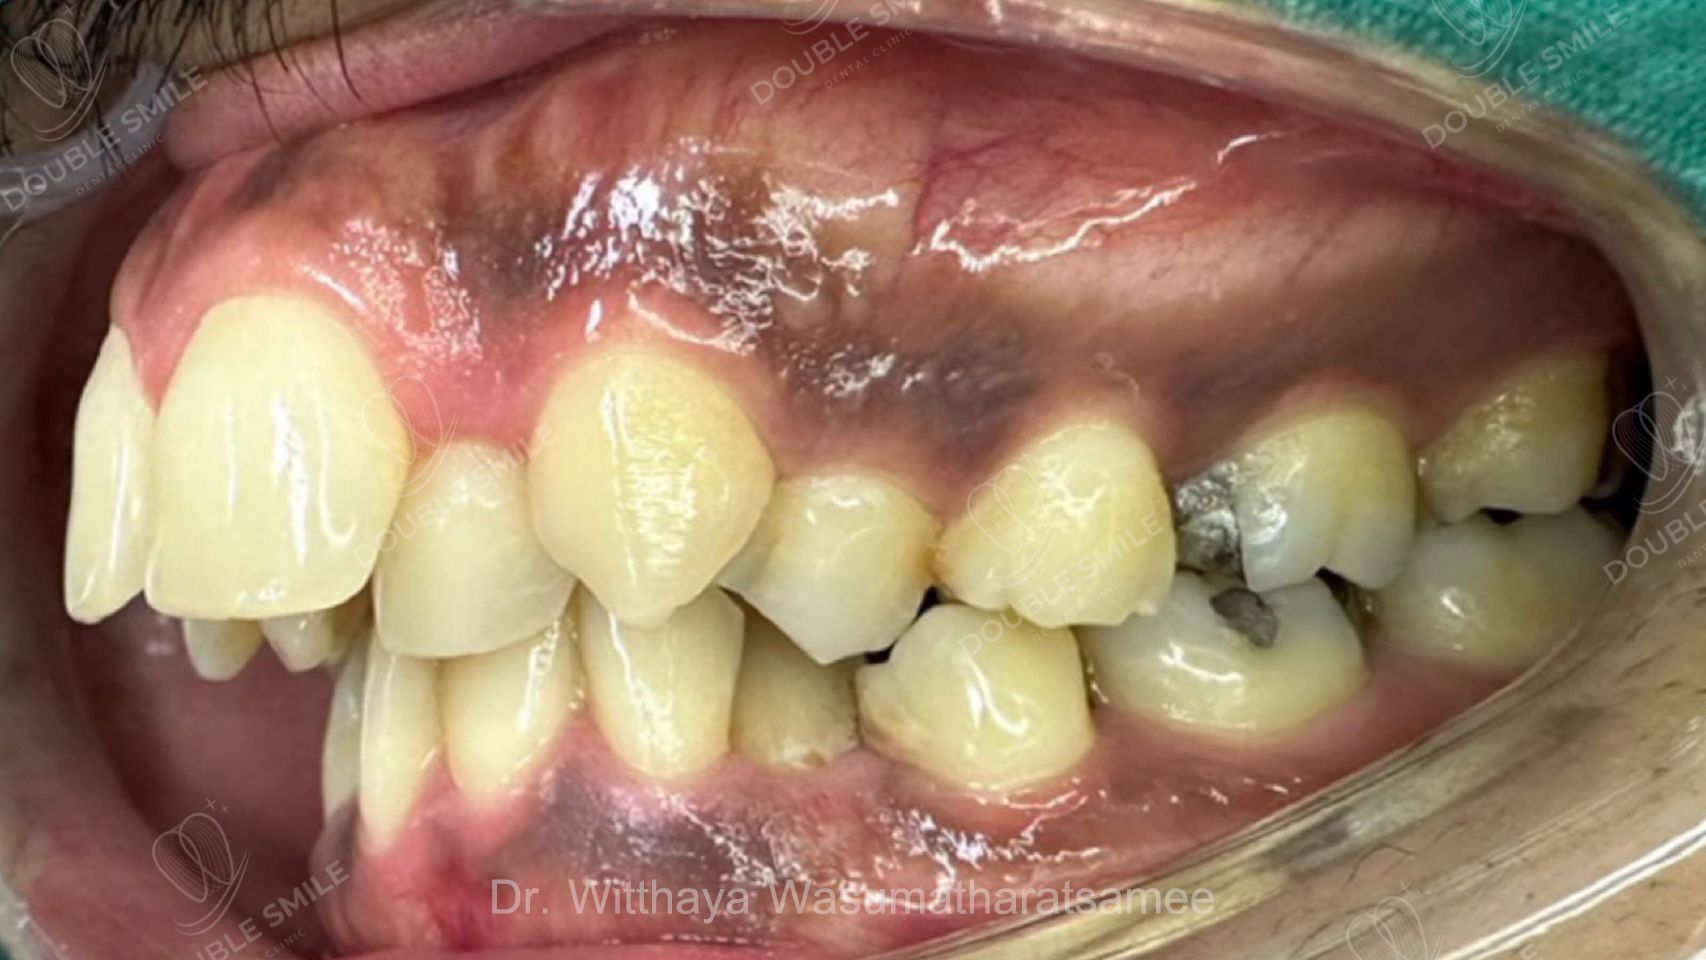

เคสรีวิวที่ 55

Before

Case Review

Before & After